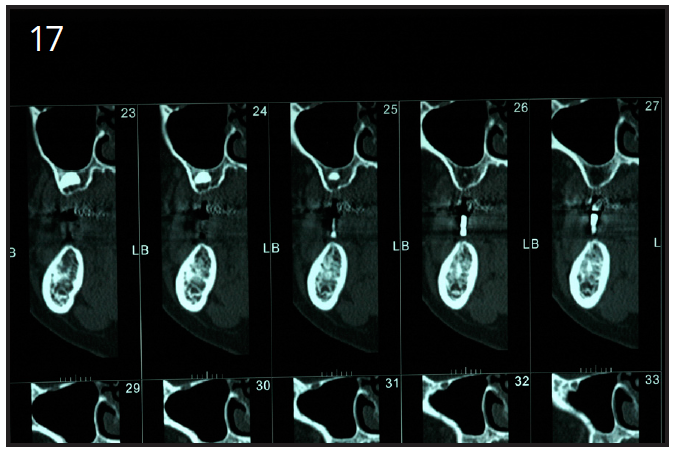

A radiographic guide may be given to the patient to wear during the jaw CT scanning procedure. This is made by the dental laboratory or in the dental office. Impressions of both arches are required to obtain mounted dental models. The correct occlusion relationship and the location of the teeth to be replaced with implants must be noted. The patient wears the radiographic guide when the CT scan is being taken. The radio-opaque markers from the radiographic guide are visualized on the CT scan, marking the position of the desired implant orientation. (Figure 17)

Figure 17 – Radiographic guide for the mandible

Figure 17